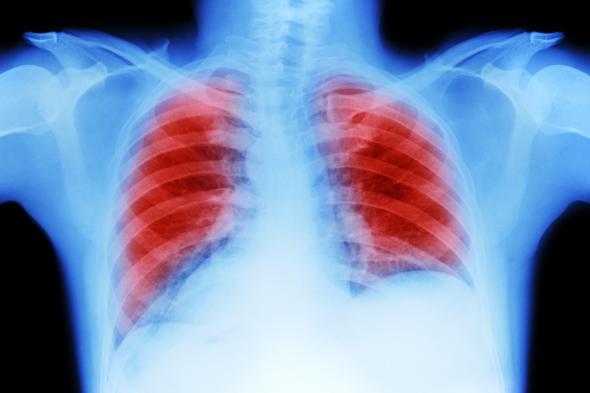

Cáncer de pulmón en una radiografía.Getty Images

"Afortunadamente, mi médico me envió a hacerme una radiografía y análisis de sangre, y esa tarde recibí una llamada diciendo que se había encontrado una 'masa' en mi pulmón izquierdo", ha contado la mujer al tabloide británico.